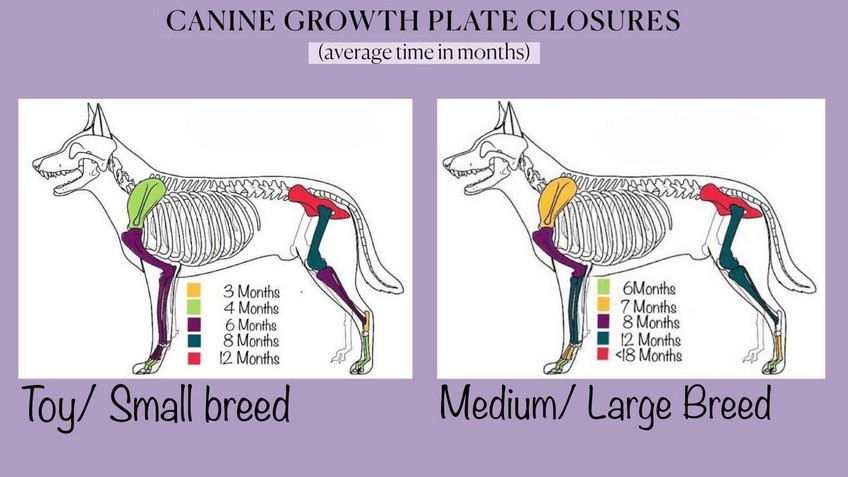

Approximate development times of a dog's skeleton on the left values relating to miniature and small breeds on the right values relating to medium and large breeds | ||

HEALTH: Since 1992 we have been doing x-rays of hip and elbow joints Together with Ala Cecrdlova, we were one of the first breeders who pushed for the introduction of the obligation of these health examinations for inclusion among the breeding conditions of retrievers in the Czech Republic. The second health aspect, which we consider very important, is the eye examination. Because we are convinced of itprinciple that the breed, which is most often used as a guide dog, must itself have completely healthy eyes. Our dogs therefore undergo a genetic test for Progressive Retinal Atrophy, Progressive Rod-Cone Degeneration (PRA-prcd). Another genetically tests which our dogs undergo: Centronuclear Myopathy (CNM) Cystinuria, Degenerative Myelopathy (DM) Exercise Induced Collapse (EIC) Hereditary Nasal Parakeratosis (HNPK) Tests of our dogs are sending for evaluation to the DDC DNA Diagnostic Center laboratory in Fairfield, Ohio, USA. Based on the results of these health tests, we then place our dogs in breedin. Also for mating of our females we choose dogs that have also passed genetic tests. Therefore we are able to guarantee future owners that a puppy from us will never get sick with any of the aforementioned genetic defects. We always inform all new owners of our puppies how important a correct and responsible approach to their development is in the first year of life. Because the skeleton and joints - his entire supporting structure - develop up to a year and a half, it is very important to maintain great patience during this period and refrain from overexerting yourself with movement. Proper nutrition is also very important during the development period. To give you a better idea - a puppy in the period up to 18 months will go through the same phase of development as a child up to 15 years old. I.e. for what a human child has 15 years = 180 months for his development, a dog puppy has has only 18 months = 10x less time for his development. That is why it´s very important to maintain a resting regime for a sufficiently long time, especially for larger and giant breeds of dogs. The Labrador, despite being classified as a medium breed, needs, due to its adult weight, the same considerations as large breeds. | ||